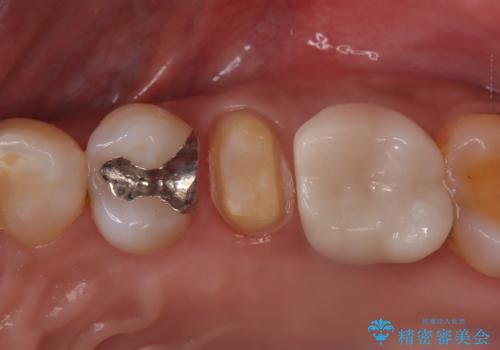

- 「何もしなくても歯が痛む、咬むと歯が痛む」を主訴に来院された患者さんです。検査の結果、歯髄の部分壊死と診断しました。根管治療を行いファイバーコアとオールセラミッククラウンで治療を行いました。

術前に神経の部分壊死と診断しましたが、神経をあけたときに出血が一切無かったので神経が死んでいるという診断は正しかったという事になります。

神経が死んでしまった原因はプラスチック(保険適用治療)の被せ物が劣化し歯と被せ物の間に生じた隙間からのリークが原因だと考えます。